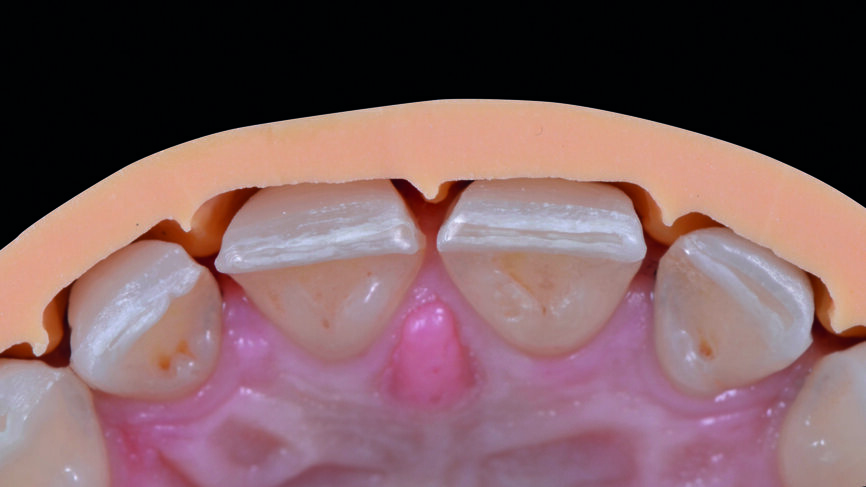

Le jeu de facettes en céramique feldspathique a été fabriqué en IPS Style (Ivoclar Vivadent) sur un modèle en plâtre-pierre, tandis qu‘un bloc IPS Empress CAD Multi (Ivoclar Vivadent) a été utilisé pour le jeu numérique (Figs. 13 et 14). Les deux jeux ont été évalués en bouche avec une pâte d‘essai afin de comparer les propriétés optiques des facettes feldspathiques et des facettes réalisées en technique CFAO (Figs. 15a–c).

Le clinicien et la patiente ont décidé subjectivement un scellement des facettes en céramique feldspathique en raison des légères différences dans la longueur des incisives centrales des deux jeux. Les procédures adhésives ont suivi (Figs. 16a–f) et des photographies intra-orales et extraorales ont finalement été prises une semaine plus tard (Figs. 17a–e).